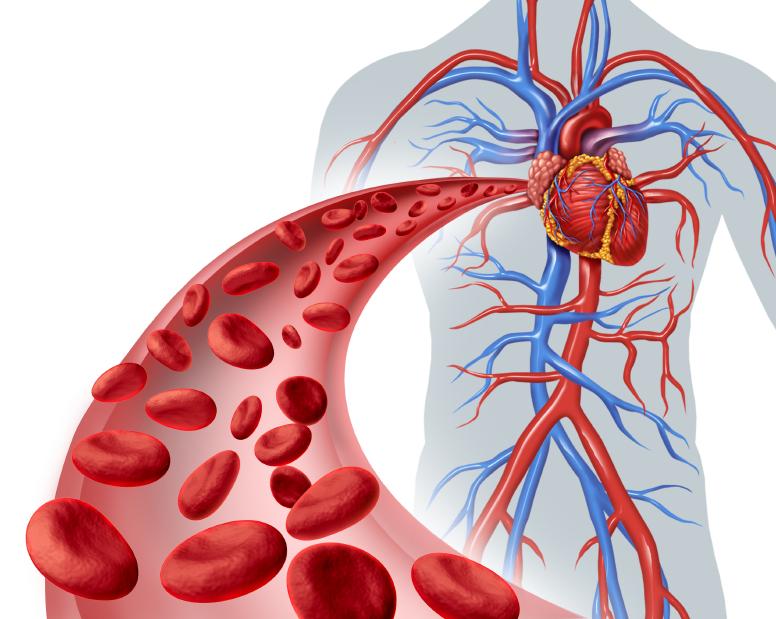

El flujo sanguíneo es la cantidad de sangre que atraviesa un punto dado de la circulación en un período de tiempo determinado. Normalmente se expresa en mililitros por minuto o litros por minuto, pero puede expresarse en mililitros por segundo o en cualquier otra unidad del flujo y de tiempo. El flujo sanguíneo global de toda la circulación de un adulto en reposo es de unos 5.000 ml/min, cantidad que se considera igual al gasto cardíaco porque es la cantidad de sangre que bombea el corazón en la aorta en cada minuto.

La sangre que bombea el corazón fluye desde la parte de presión alta de la circulación sistémica (es decir, la aorta) hacia el lado de baja presión (es decir, la vena cava) a través de muchos miles de vasos sanguíneos dispuestos en serie y en paralelo. Las arterias, arteriolas, capilares, vénulas y venas se disponen colectivamente en serie.